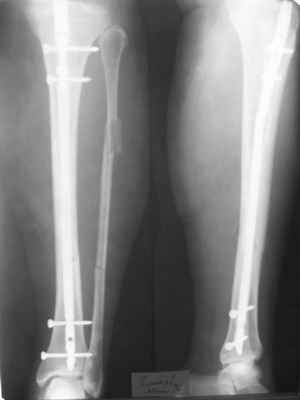

Здравствуйте уважаемые коллеги. Позвольте поделиться опытом применения интрамедуллярного остеосинтеза большеберцовой кости имплантатами компании ?Остеомед" с запатентованной прицельно-навигационной системой для дистального блокирования ?Интерлок". Для определения длинны и диаметра стержня использовали линейку-шаблон, позволяющей с легкостью рассчитать длину и диаметр стержня с проекцинно искаженными размерами, как конечности, так и линейки-шаблона.Дистракцию производили с помощью спицевого дистрактора с последующей закрытой репозицией отломков винтами Шанца. Все основные этапы производили по методике АО, гарантированное дистальное блокирование достигается за счет центрирования отверстий, путем контролирования смещения стержня в костномозговом канале в сагиттальной плоскости. Клинический пример:Больная Я. 45 лет, пострадала в результате случайного падения на улице 19.12.2005., имеет место открытый 1 степени перелом обеих костей левой голени со смещением отломков.произведена закрытая репозиция перелома с последующим введением стержня (на данном этапе производился рентген-контроль)Убедившись в достаточной репозиции перелома, произведено дистальное и проксимальное блокирование интрамедуллярного стержня.Общее время затраченное на оперативное вмешательство составило 45 минут.